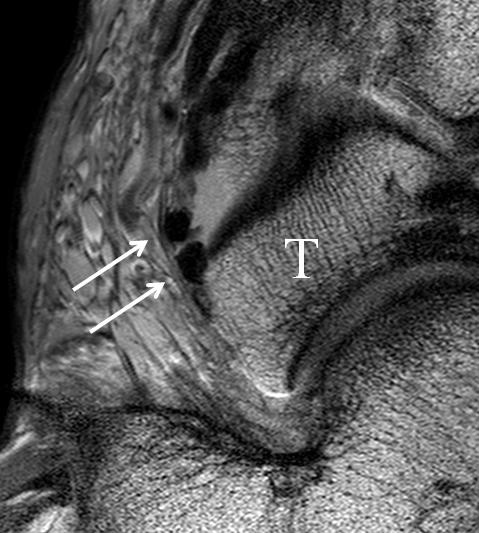

Das Ligamentum tibiofibulare posterius (hintere Syndesmose) verläuft flacher und geht nach kranial in das Ligamentum tibiofibulare interosseus und nach kaudal in das Ligamentum intermalleolare posterius über. Letzteres bildet ein artikuläres Labrum zwischen Trochlea und Talus 9.

Da also die hintere Syndesmose an der posterioren Tibia inseriert, entspricht eine Fraktur oder Infraktion des hinteren Volkmann`schen Dreiecks funktionell einem knöchernen Ausriss des Ligamentum tibiofibulare posterius (Abb. 18 a und b). Aufgrund der Koinzidenz von Syndesmosenläsionen mit Innenbandverletzungen ist bei der Beurteilung gesondert auf solche zu achten.

b. T2 fs axial. Infraktion des hinteren Volkmann‘schen Dreiecks (schmale, weiße Pfeile). Hier inserierende, intakte, hintere Syndesmose (breite, weiße Pfeile).